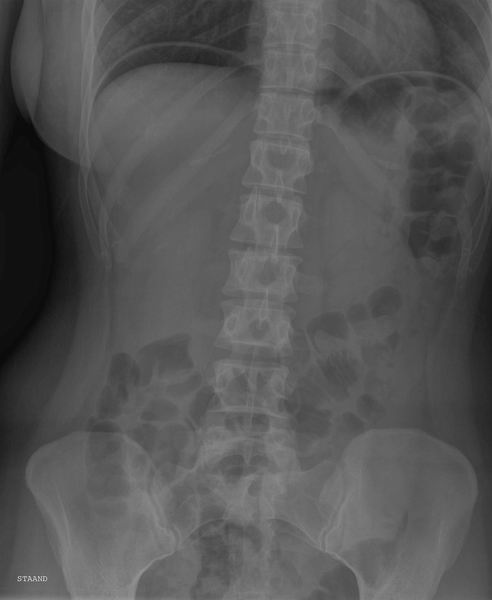

Full leg